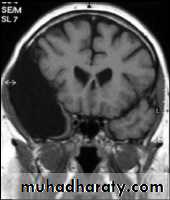

Sagital section of brain ( T1 w post contrast injection)

CORONAL SECTION OF BRAIN ( T1w post contrast injection)